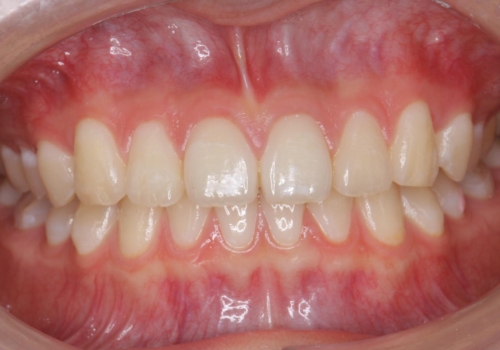

低予算、短期間で治療も終了し、大変満足していただきました。

全体矯正をしていないため、就寝時にリテーナー使用は継続していただくことになっています。

全体矯正ではなく部分矯正で治療することになりました。

その代わり、すき間をすべて閉じるのは難しく、両脇の目立たないところに集めて治療終了しています。